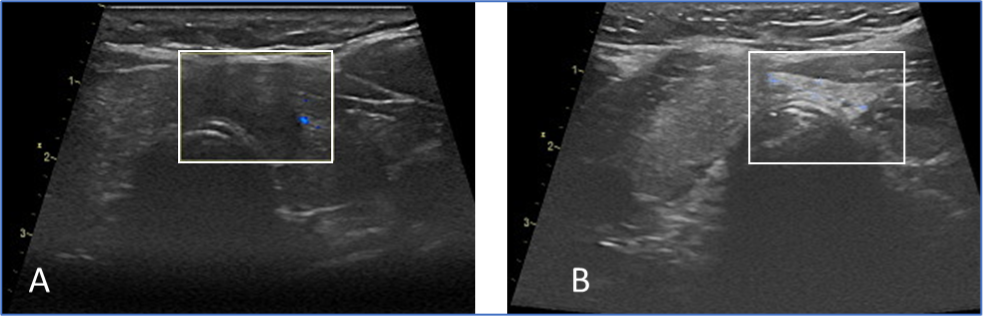

До (А) и после (B) лечения кисты щитовидной железы. После терапии киста больше не заполняется.